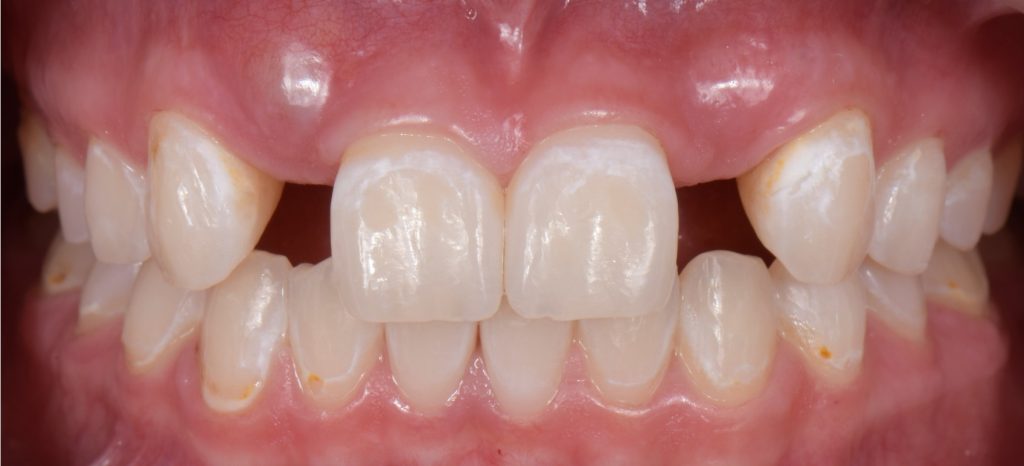

Solution #2: Resin-Bonded Fixed Dental Prostheses (RBFDP)

RBFDP is a proven solution for congenitally missing lateral incisors (Figs. 2-12). Although it is considered an interim restoration, the literature provides substantial evidence supporting its long-term potential. However, the clinical performance of an RBFDP is significantly superior to that of a bilateral retainer, and the dissimilar mobility of the abutment teeth explains this.

When placing an RBFDP from a central incisor to a canine, each abutment wants to move under occlusal load, but because of the position each tooth occupies in the arch, loading occurs in different vectors, therefore, leading to debonding of the retainer of the abutment tooth with the least mobility. When considering which one of the adjacent teeth will work best as the abutment, the clinician needs to evaluate:

From an occlusal standpoint, patients with shallow overbites or a large amount of overjet make better candidates for RBFDP, and the pontics should be avoided in all lateral excursions, including crossover.

Space requirements and connector dimensions depend on material selection. Utilizing zirconia has been proven to be more predictable over time, and recommended connector dimensions are:

The amount of tooth reduction is based on available interocclusal space, and often, there is enough space requiring minimal preparation. The key is to stay in enamel. It is also advisable to stay 2.0 mm away from the incisal edge so that the zirconia retainer does not affect the translucency of the natural tooth.

If the patient has a deep overbite, proclined teeth, or mobile abutment teeth, an RBFPD may not be the best treatment option. This is why they are often used as a long-term provisional until the patient is old enough to have an implant placed.